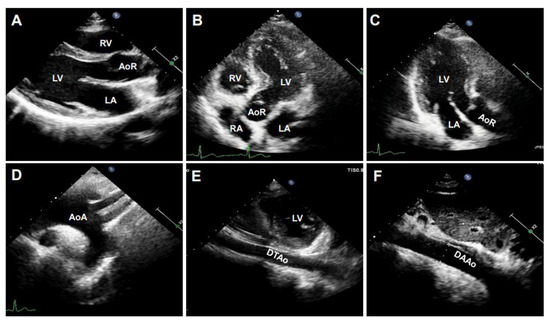

B-mode ultrasonography, also known as two-dimensional (2D) ultrasonography, is one of the most basic ultrasound models that produces a real-time black/white image of the targeted site, where the aortic wall is shown as echo-reflecting and the lumen as echo-free. As shown in Figure 3, the ultrasonographic view of the aorta is either circular in the perpendicular sections or tube-shaped in the parallel sections in humans. For example, the AoR and the AAo could be visualized in the parasternal long-axis view (Figure 3A), the modified right parasternal long-axis view, modified apical five-chamber (Figure 3B), and three-chamber views (Figure 3C). Additionally, the suprasternal view is a crucial view to visualize the AoA and the three supra-aortic trunks (innominate, left carotid, and left subclavian arteries), and a variable tract of the AAo and the DTAo (Figure 3D). In some cases, the entire arch could not be visualized in a single image plane because of the aorta’s extreme tortuosity. The DTAo can also be displayed in the posterior field through the cardiac acoustic window (Figure 3E). Moreover, parts of the DTAo may be invisible due to the tracheal air. The subcostal views may be helpful and allow the DAAo to be visualized (Figure 3F). Although B-mode has been widely used in humans, its application in mouse aorta remains relatively challenging, primarily because of the difficulty in obtaining exceptional spatial and temporal resolution in a small, rapidly varying vessel. Since apical views of the heart are prone to change in rodents, particularly in mice, it is difficult to obtain stable images of the aorta in this view. Reciprocally, the parasternal (Figure 4A), suprasternal (Figure 4B), subcostal, and transabdominal views (Figure 4C) are the most critical views for murine aorta, which enable an adequate assessment of the AoR, the AAo, and most of the segments of the DTAo and DAAo in mouse models.

Figure 3. The representative images of human aorta segments were obtained by B-mode. The segments of the aorta were imaged from a 20-year-old male volunteer. (A): The parasternal long-axis view of the aortic root (AoR). (B): The apical five-chamber view of the AoR. (C): The apical three-chamber view of the AoR. (D): The suprasternal view of the aortic arch (AoA). (E): The parasternal view of the descending thoracic aorta (DTAo). (F): The subcostal view of the descending abdominal aorta (DAAo). LV: left ventricle, LA: left atrium, RV: right ventricle, RA: right atrium.